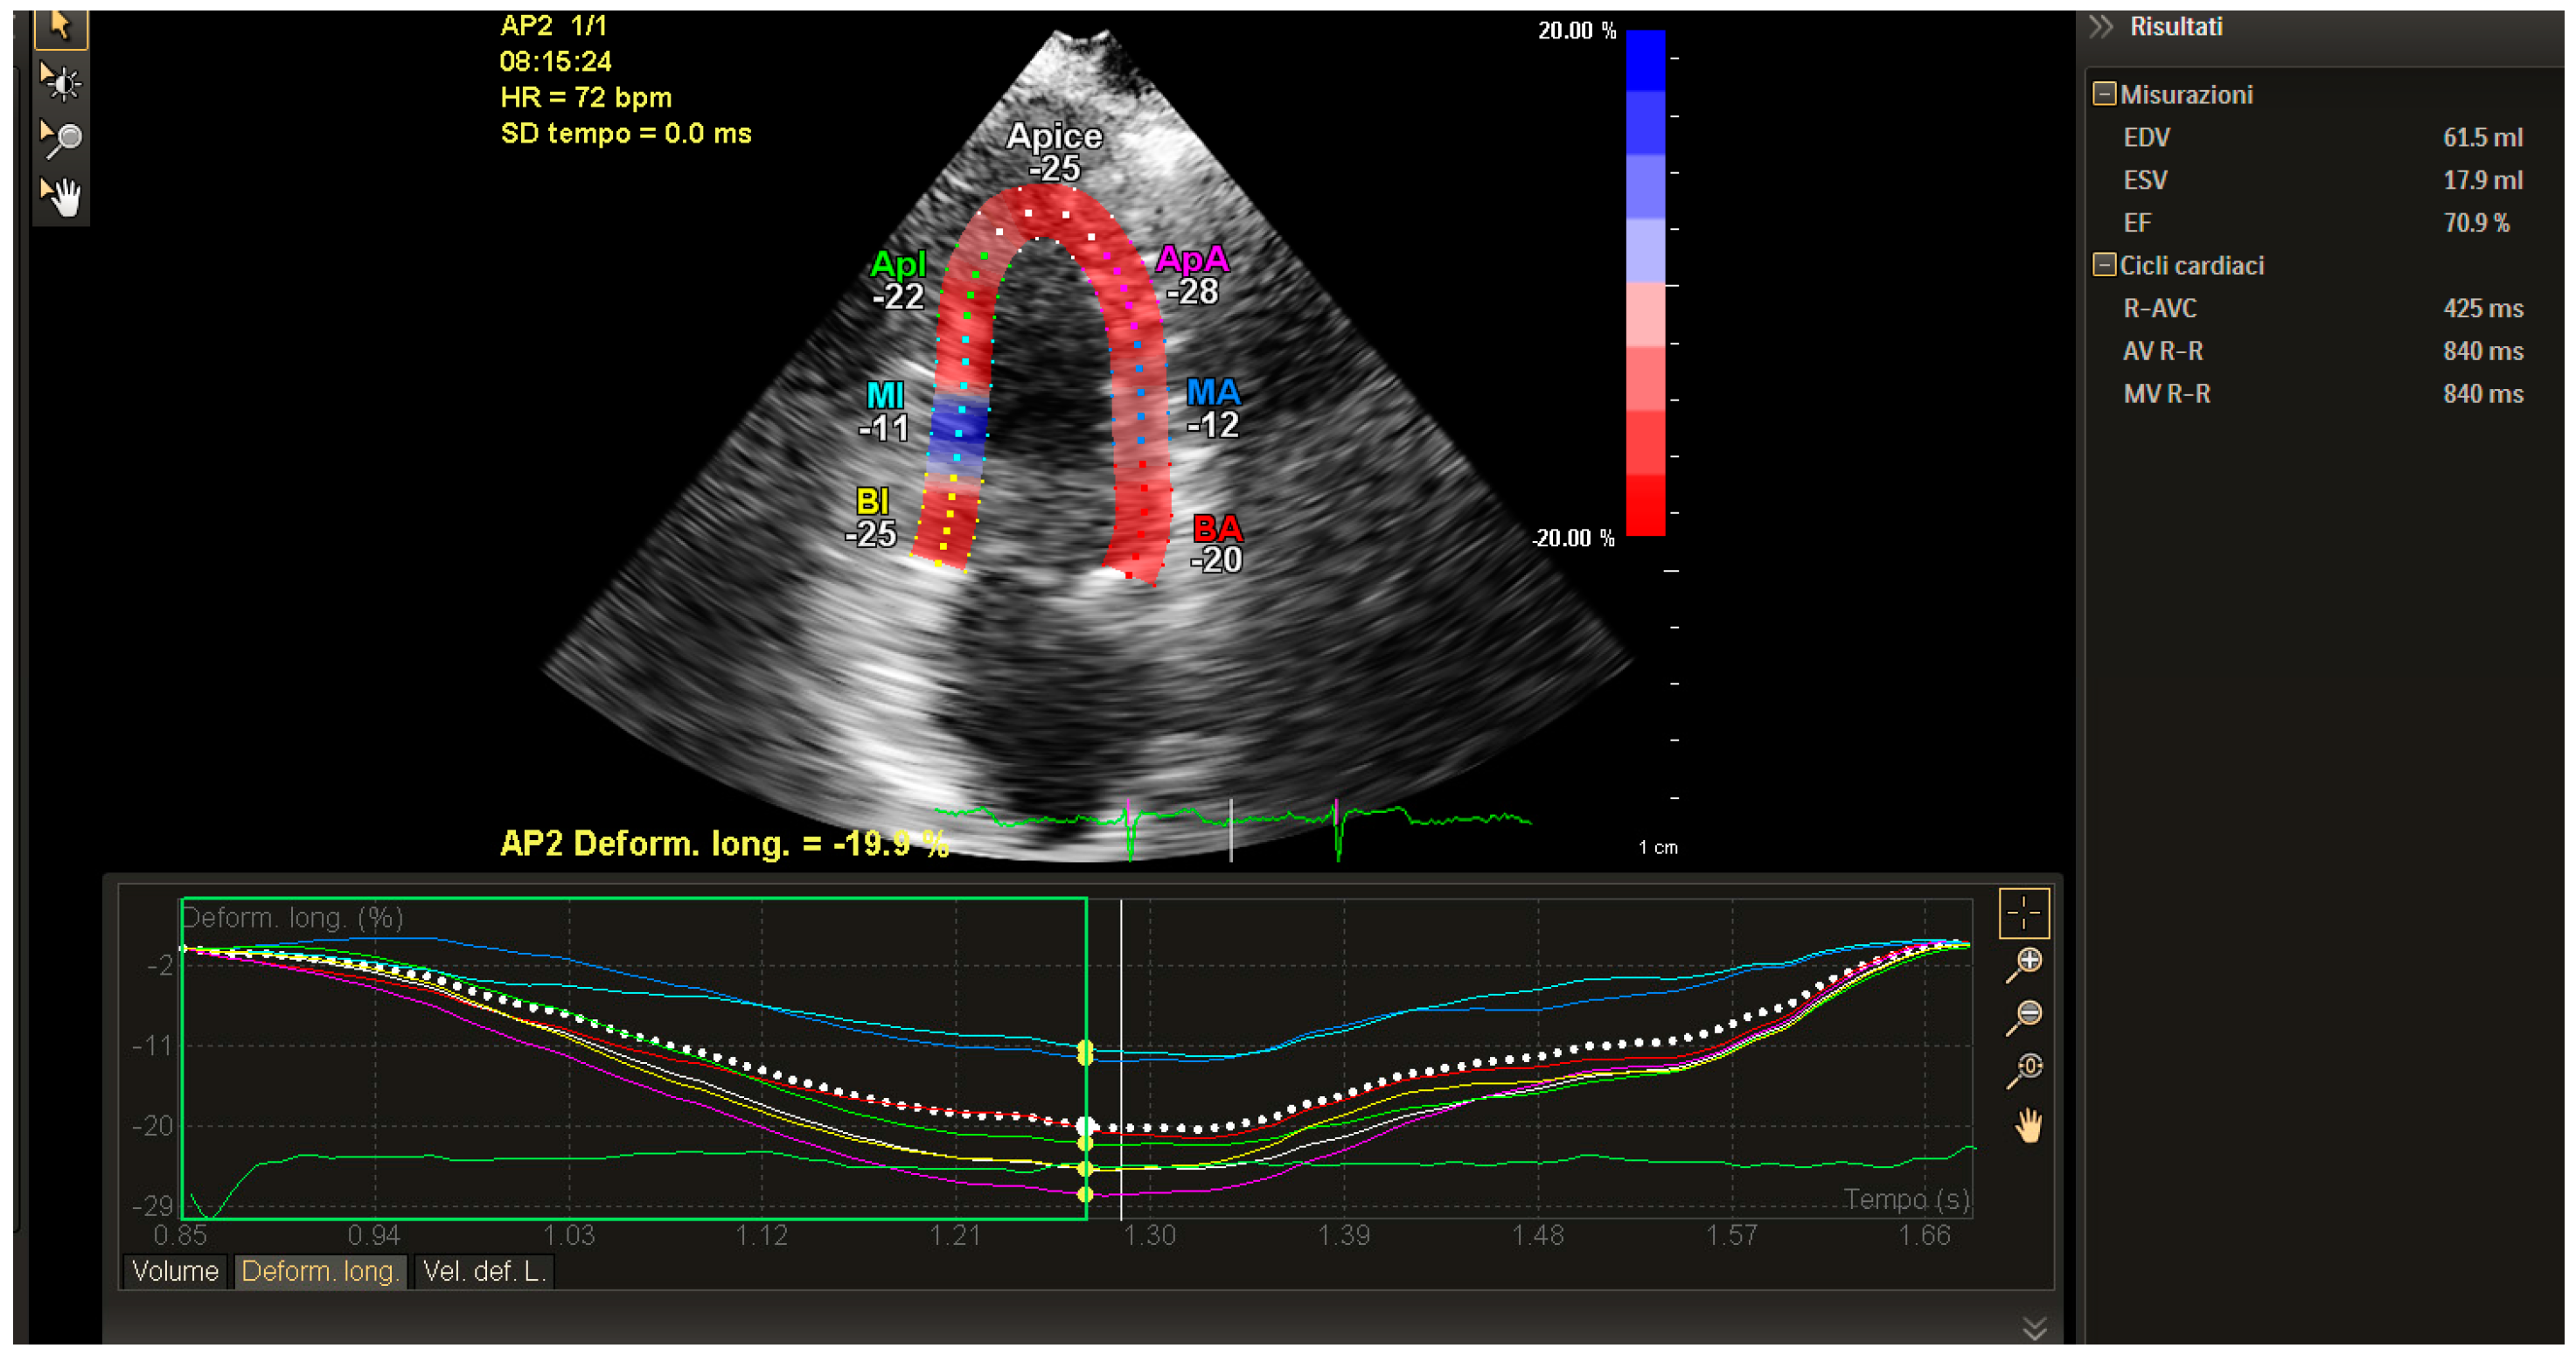

Figure 2.

GLS of LV in breast cancer patient. Two-chamber view. The image shows the strain values obtained by the post processing analysis performed by Q-station, after 5X-1Strain software image acquisition. The software is included in the iE33 Philips echocardiography. The acquisition has been made from a two-chamber view. The global and segmental values are within the normal and validated range despite being at the lower limits.